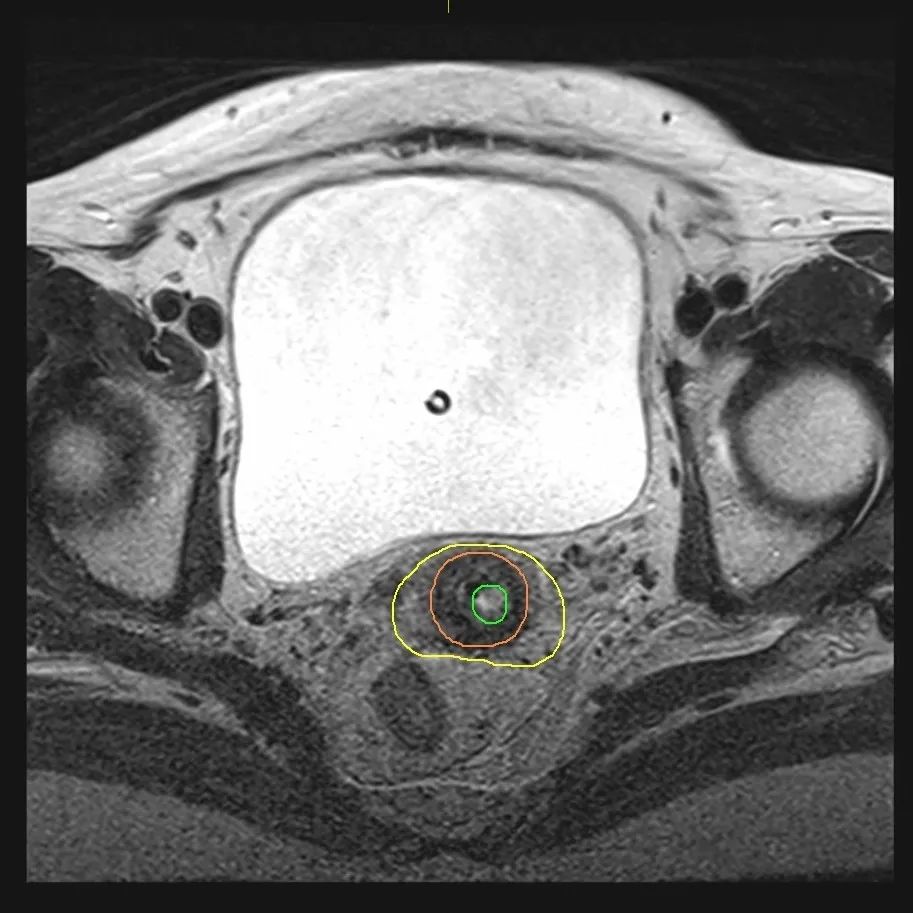

核磁共振較CT有更高的軟組織分辨率,可有效去除金屬偽影,在精確腫瘤靶區(qū)及保護(hù)正常組織器官上具有獨(dú)特的優(yōu)勢(shì)。同時(shí),核磁共振定位對(duì)施源器或插植針有特殊要求。此次治療使用了鈦合金材料的宮腔管,雙側(cè)宮旁組織分別置入兩根非磁性柔性插植針,針內(nèi)置入水性材料定位纜,完美滿(mǎn)足了核磁共振掃描成像要求。

(后裝治療前核磁共振定位)

(核磁共振圖像)